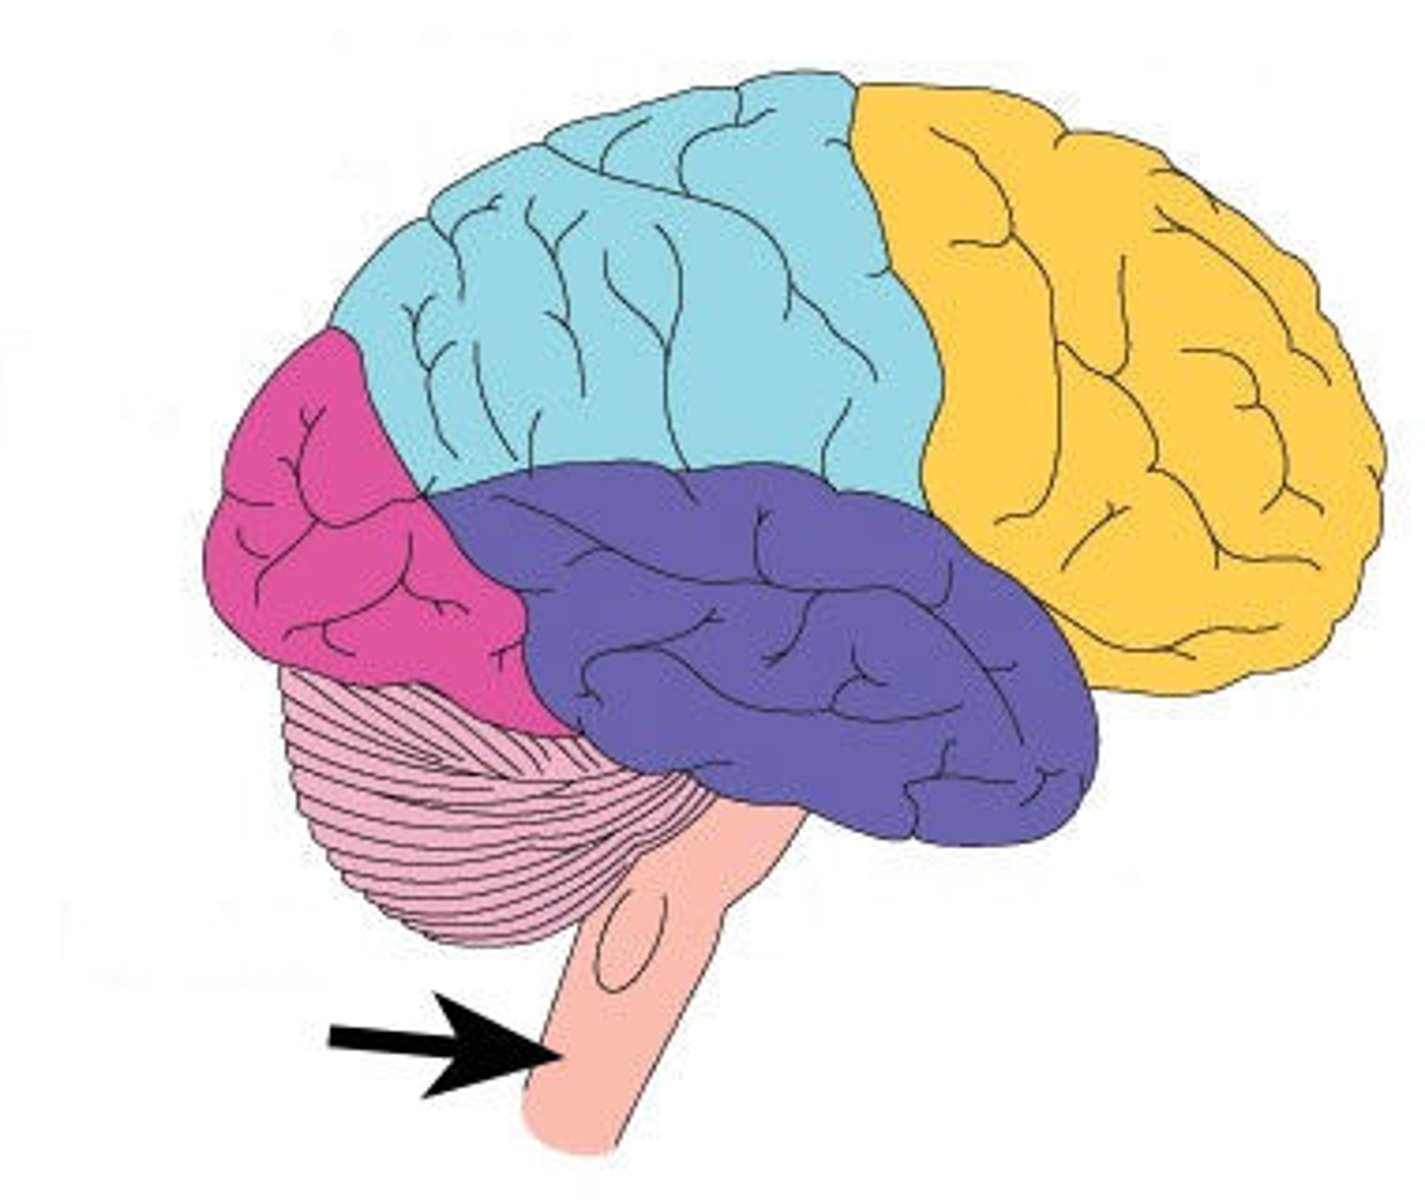

tentorium cerebelli

2nd largest, crescent-shaped, separates cerebrum (occipital lobes) from cerebellum (arrow #5)

falx cerebelli

seperates the two hemispheres of the cerebellum. it lies inferior to the tentorium cerebelli, separating cerebellar hemispheres (arrow #7)

diaphragm sellae

smallest infolding covering pituitary gland & sella turcica